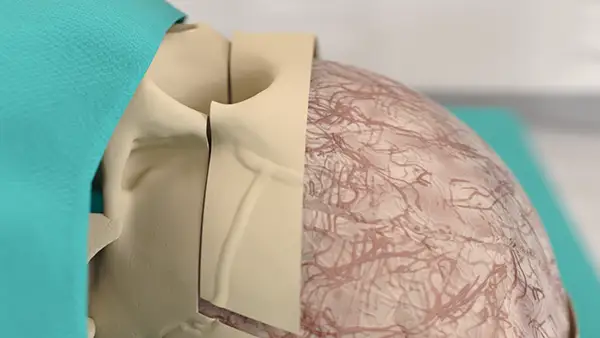

Craniotomy

and craniectomy

Details

Reduced risk of CSF leak, better aesthetic result for the patient, sparing of fixation materials, dural and bone substitutes, due to selective and precise cutting.

Reduced heat ensures improved ossification with implants.